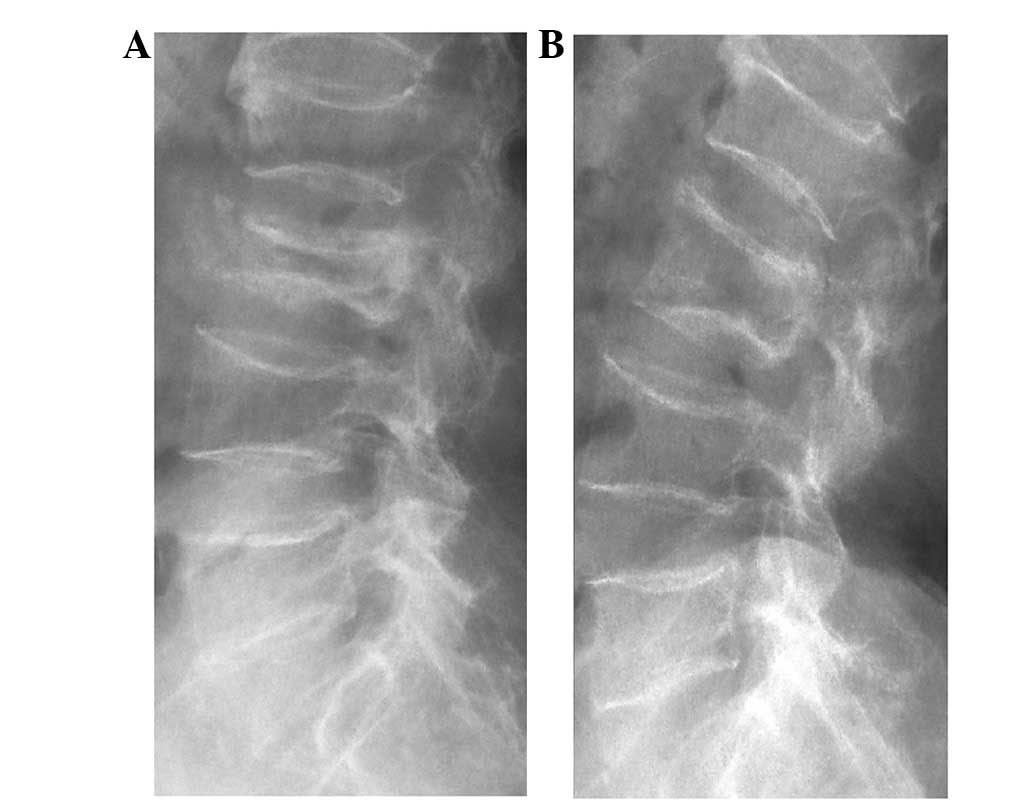

The Intravertebral Vacuum Cleft Sign Appears As A Transverse Linear Or Download Scientific Diagram